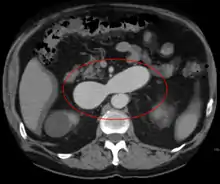

AVMs are diagnosed primarily by the following imaging methods:[12]

- Computerized tomography (CT) scan is a noninvasive X-ray to view the anatomical structures within the brain to detect blood in or around the brain. A newer technology called CT angiography involves the injection of contrast into the blood stream to view the arteries of the brain. This type of test provides the best pictures of blood vessels through angiography and soft tissues through CT.